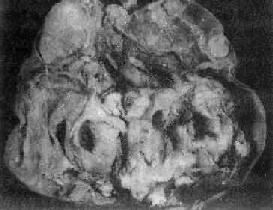

图13-22 卵巢囊性畸胎瘤 囊内充满含有毛发的黄色油脂样物 囊性畸胎瘤预后好,少数可发生恶性变,最常见者恶变为鳞癌。恶性变常发生在囊壁内头节附近,故检查时应注意取材部位。 2.未成熟型畸胎瘤(teratoma,immature type)此型较少见,仅占卵巢畸胎瘤的1%~3%。多见于25岁以下的年轻患者。 【病变】 肉眼观,肿瘤多为单侧性,体积一般较大,结节状,切面多为实性,夹杂有单个或多个大小不等的囊性部分。实性部分常为杂色,灰白、棕色或黄色,质软而脆,常有出血坏死。镜检可见由三胚层分化而来的未成熟和成熟组织混合组成。常见的未成熟组织为神经组织,如原始神经上皮和室管膜等结构及各种胚胎性组织,如胚胎性骨、软骨及肌肉等。皮肤组织较成熟型少见。其中可混杂一些各胚层的成熟组织。 未成熟型畸胎瘤常合并其他生殖细胞肿瘤,如内胚窦瘤、无性细胞瘤及绒癌等。一般说,肿瘤组织中未成熟组织及胚胎性组织的含量与临床恶性程度有关。病理上根据未成熟组织的含量,可分3级:①1级,主要为成熟组织,有少量未成熟组织,没有神经上皮或每一切片中神经上皮不超过一个高倍视野;②2级,有较多未成熟组织,每一切片中所含神经上皮不超过1~3个高倍视野;③3级,未成熟组织量多,每一切片中神经上皮超过4个高倍视野。 预后 未成熟畸胎瘤的预后与病理分级、临床分期密切相关。复发及转移者多为2、3级。转移的部位多在盆腔及腹腔内,远处转移极少。 (二)无性细胞瘤 无性细胞瘤(dysgerminoma),较少见,约占卵巢恶性肿瘤的1%~2%,多见于10~25岁年轻妇女。 【病变】 肉眼观,常为单侧性,约10%为双侧性。肿瘤多为圆或卵圆形,表面光滑,质韧。切面多为实性,有不同程度的出血坏死或囊性变,色灰红、暗红及棕黄色。镜下,与典型的睾丸精原细胞瘤非常相似,瘤细胞体积大而圆,比较一致,胞浆因含糖原而透明。核大,圆或卵圆形,大小形态一致,小泡状,核仁明显,核分裂像常见。瘤细胞排列成片块、巢状或条索。瘤细胞间常有不等量的淋巴细胞浸润及多少不等的纤维组织。由于肿瘤细胞形态和组织化学特性与未分性别的原始生殖细胞极相似,故命名为无性细胞瘤。 本瘤预后较好,对放射线敏感,5年生存率90%~95%。约5%病人对侧卵巢在显微镜下才能发现肿瘤,因此手术时必须进行活检,作冷冻切片检查。 肿瘤可直接蔓延扩散至盆腔附近器官及通过淋巴系播散到腹膜后及主动脉旁淋巴结等,晚期也可经血行播散到肺及肝等。 (三)内胚窦瘤 内胚窦瘤(endodermal sinus tumor)又称卵黄囊瘤(yolk sac tumor),来源于多能的生殖细胞,向胚外结构方向分化而形成的一种高度恶性的生殖细胞肿瘤。多见于儿童及年轻妇女,平均年龄18岁。除卵巢外,还可发生于骶尾、腹膜后、纵隔、松果体等处。 【病变】 肉眼观,肿瘤多为单侧性,以右侧为多,一般体积较大,平均直径为15~25cm,圆或卵圆形,表面光滑。切面多为实性,质较脆,灰白或粉白色,常有出血坏死及囊性变。镜检,组织形态较复杂及特殊,主要特征有下列几点:①网状结构,是最常见的形态,由星芒状的瘤细胞形成疏松网状结构(图13-23),其中有微型小囊或间隙,囊腔被覆扁平或立方细胞,这种结构类似胚外中胚层结构;②内胚窦样结构,立方或柱状的瘤细胞成单层排列,包绕毛细血管,形成一血管套样结构,这种结构横切面很像肾小球,称为Schiller-Duval小体,这种小体和大鼠胎盘内的Duval内胚窦结构相似,这种结构可能是由卵黄囊衍生演变而来;③多泡性卵黄囊样结构,特征是由扁平上皮、立方或低柱状的瘤细胞形成大小不等的囊腔,其间隔以致密的结缔组织或疏松的粘液样间质,这种结构与胚胎时期的卵黄囊(胚外内胚层)相似;④在瘤细胞内及瘤细胞间隙可见PAS阳性的大小不等的嗜酸性小滴,免疫组化显示这种小滴含有甲胎蛋白(AFP),正常情况下,卵黄囊可合成AFP;⑤可见腺样、乳头状及实体细胞团结构等。

图13-23 内胚窦瘤 呈疏松网状粘液瘤样结构,其中有互相沟通、衬以上皮的腔隙及小囊腔,在瘤细胞内外可见嗜酸性玻璃样小球及基底膜样物 本瘤恶性度很高,预后差,对放射线不敏感。近年应用联合化疗后,3年存活率约13%。转移途径为直接浸润及种植扩散,偶有淋巴结转移,极少血行转移。 (四)胚胎性癌 胚胎性癌(embryonal carcinoma)为来自具有向胚外或胚内结构分化潜能的原始生殖细胞的一种未分化癌。较罕见,约占卵巢恶性生殖细胞瘤的5%。多见于儿童及青年,平均年龄为15岁。 【病变】 肉眼观,肿瘤一般为单侧性,体积较大,平均直径17cm,实性。切面棕褐或灰白色,常见出血坏死及囊性变。镜下,瘤细胞为大而幼稚的多形性细胞,胞浆中性呈不同程度的空泡状。核大而圆,空泡状,染色质粗,核仁明显,1至多个,核分裂像多见。瘤细胞排列呈实性巢状或腺泡、管状或乳头状,并常见散在的像合体滋养层细胞的多核巨细胞。免疫组化染色显示这种巨细胞含有绒毛膜促性腺激素(HCG),非巨细胞性瘤细胞内含有甲胎蛋白。 本癌为高度恶性,预后差,早期即可向局部器官和腹膜浸润,或通过淋巴道播散。5年存活率39%。